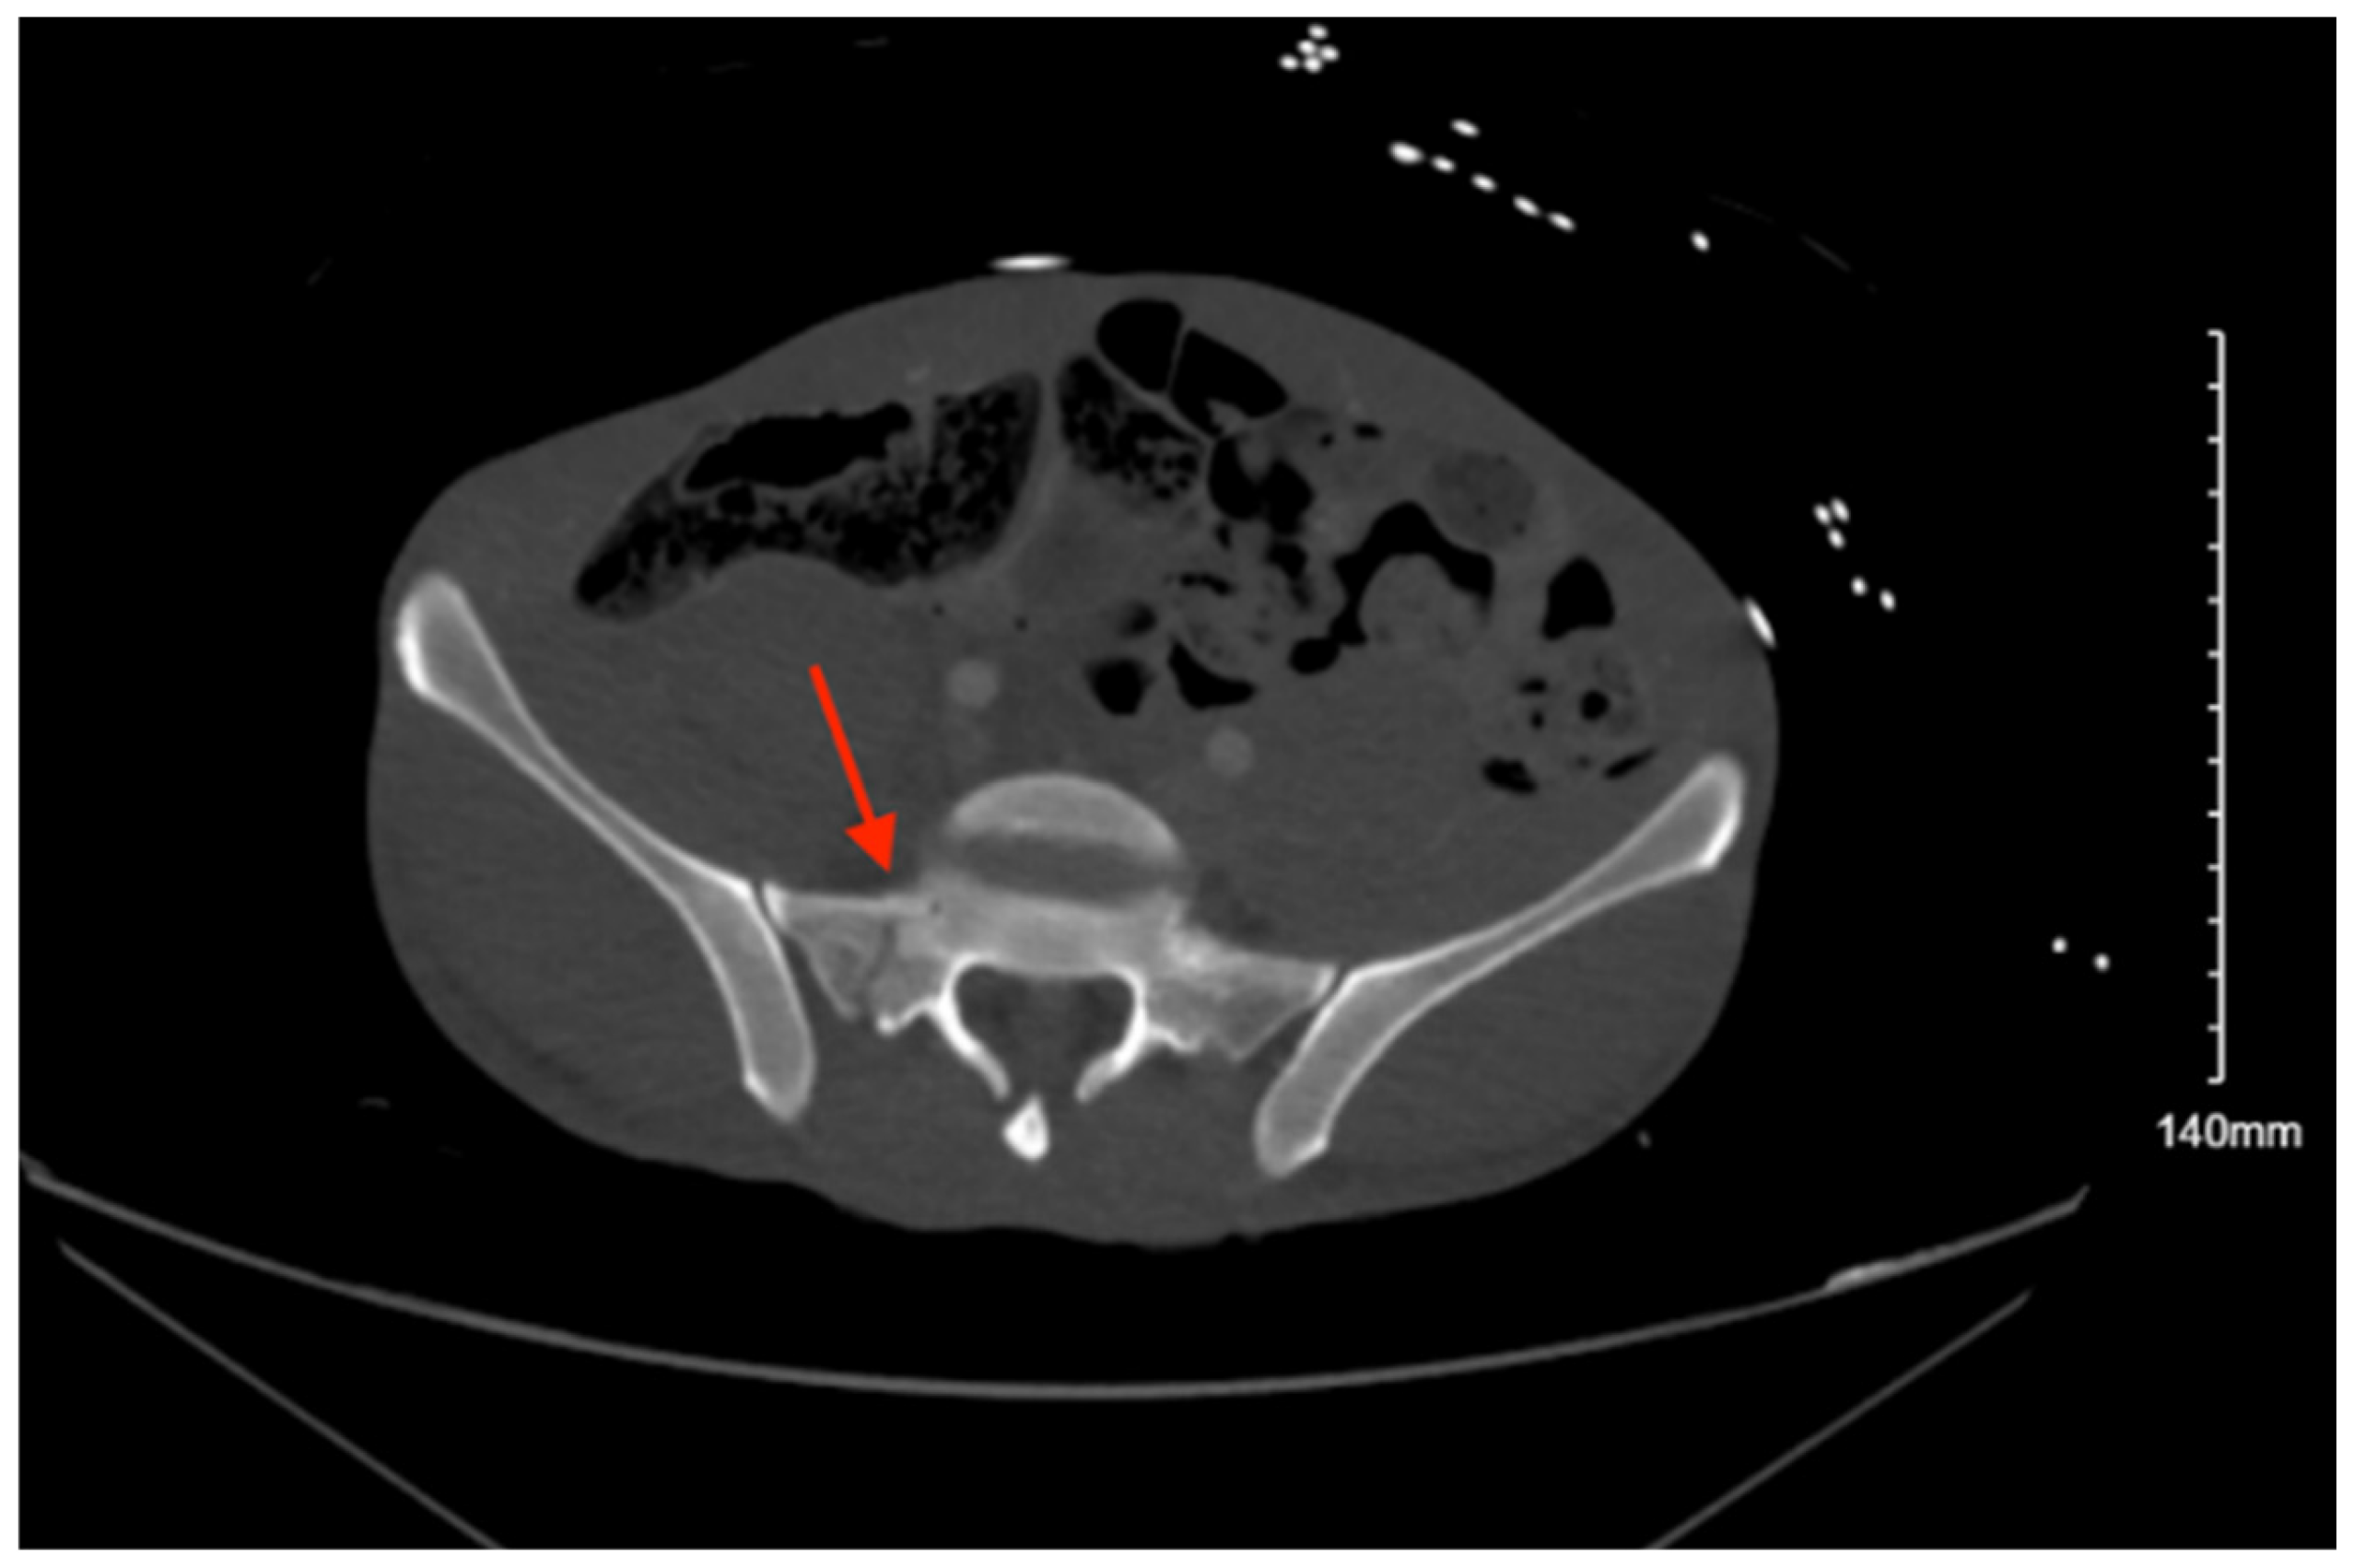

Pelvic imaging showed a fracture of the distal portion of the sacrum with anterior displacement, a comminuted fracture through the right iliac bone with moderate displacement, a moderately displaced fracture through the right inferior pubic ramus, and mildly displaced fractures of the right anterior and posterior acetabulum that involve the articular surface. There is a hemorrhage surrounding the right iliac fracture, a small volume hemorrhage in the right pelvic sidewall and the presacral space, and a small volume hemorrhage surrounding the urinary bladder (Figure 3).

Figure 3. CT abdomen/pelvis images of the described fractures in case 3. Red arrows are used to indicate the location of pelvic fractures for easier identification.